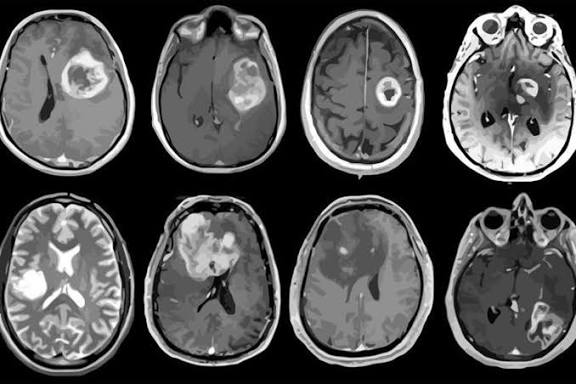

Nuevo tratamiento experimental logra resultados asombrosos contra el agresivo cáncer cerebral glioblastoma

Un estudio realizado por el Massachusetts General Cancer Center y publicado en 2024 ha generado gran expectativa en la comunidad médica.